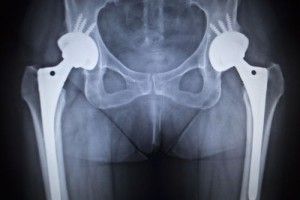

biomet-hip-replacementA Massachusetts woman who previously settled allegations about a defective met-on-metal hip is going back to court, alleging she was not properly paid.

Cheryl received a Biomet M2A Magnum hip implant and soon after began experiencing complications. High levels of chromium and cobalt were found in her blood, in addition to as well as the diagnosis of metallosis (metallic debris buildup in soft tissue).

In December 2012, Cheryl underwent a surgery to remove the old hip implant and put a new one in its place.